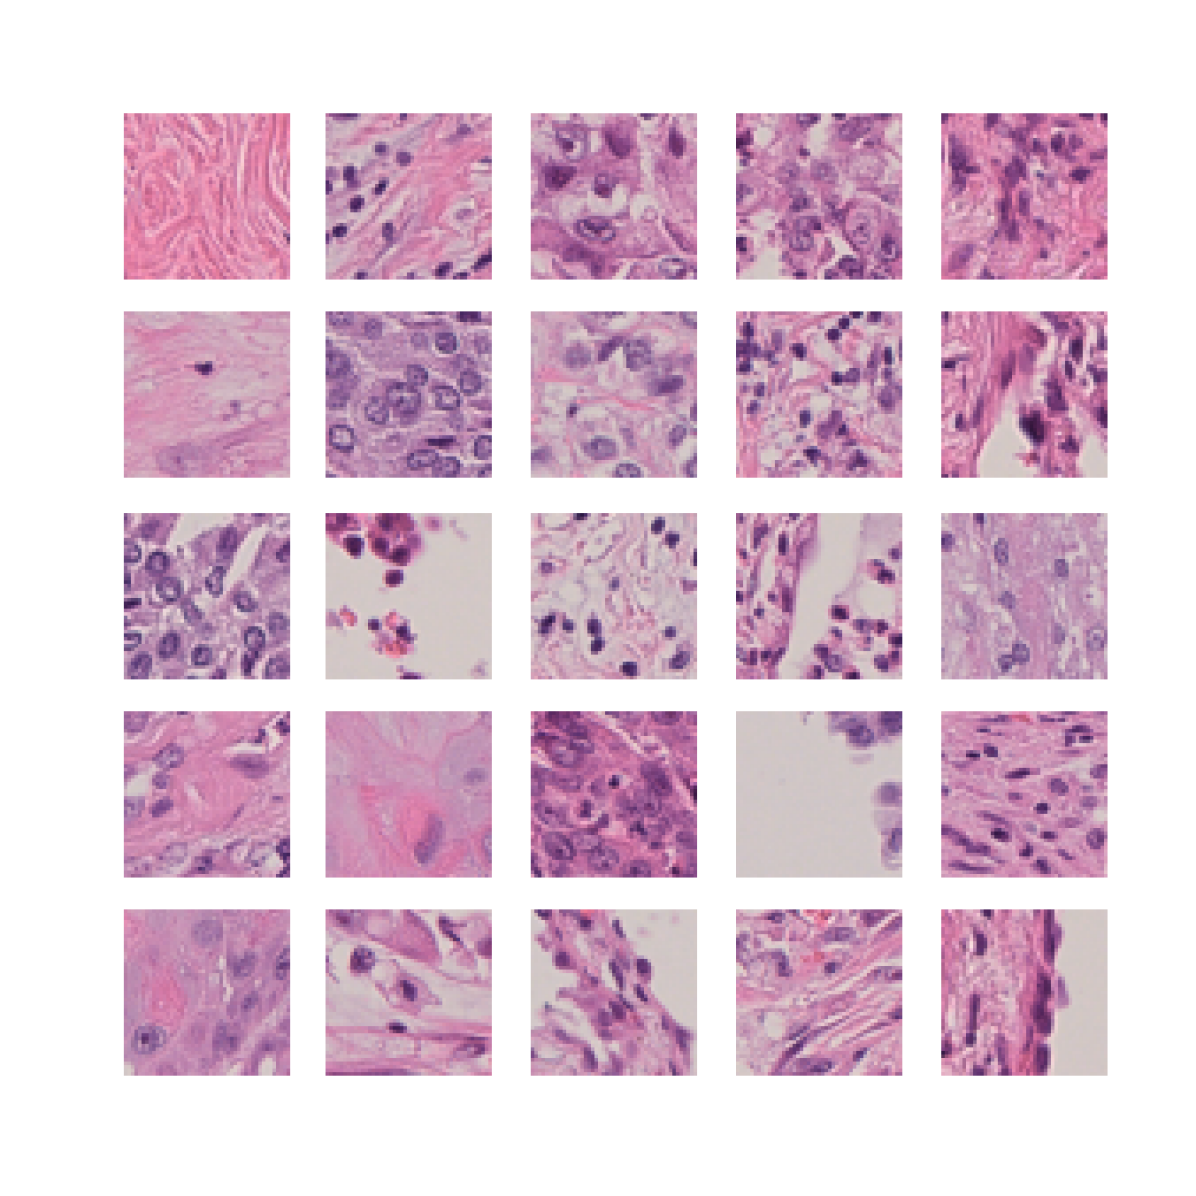

We first demonstrate that TriDeNT ♆ is highly effective for improving the quality of representations in the primary encoder by distilling privileged information from immunofluorescence (IF) images to H&E stained images (Figure 2 and Table S6). Models are trained on the SegPath dataset [22], which consists of eight subsets of H&E images paired with an image derived from the IF stain of a consecutive slice for one of eight antibodies. Evaluation is performed on four standard computational pathology tasks (see Section S2 for full details). We find that the model significantly increases performance by up to 101% compared to a privileged baseline model. TriDeNT ♆ retains not only the useful features shared between inputs, but also the features which are only present in the primary data, leading to better performance on all evaluated tasks. Even in cases where the privileged data does not appear to significantly improve performance, such as staining with CD235a, TriDeNT ♆ still achieves comparable performance, as it obtains a strong supervisory signal from the additional H&E branch. This is in contrast with the privileged Siamese setting, where it is clear that the pairing can cause a seismic drop in classification accuracy if the privileged data is not informative for the task being evaluated.

To further analyse the learned representations, we produce UMAP projections of the latent space labelled with the tissue types for the NCT tissue type classification task, as shown for CD3CD20 and SMA in Figure 4(a), and for all SegPath stains in Figures S8 and S9. These figures make the reasons for the varying performance of the privileged Siamese model more apparent. For stains with better performing privileged Siamese models, such as SMA, the UMAPs are very similar between Siamese methods and TriDeNT, with well-differentiated tissue type clusters. In those with worse performance, such as ERG, the tissue types are poorly differentiated, often with only adipose and background forming distinct clusters from the other classes. On closer inspection, it is notable in these projections that TriDeNT ♆ produces more well-defined and separated clusters in general than Siamese networks. This is further evidenced in Figure S7, where TriDeNT ♆ is shown to identify clusters with overexpression of a given gene significantly more effectively than an unprivileged Siamese model.

We also analyse the activation maps for each model using GradCAM as described in section S3. This offers more insight into the areas of the image which are contributing most heavily to the models’ representations. In Figure 4(b) we present some representative examples, however, a larger selection which was chosen at random is presented in Figures S10 to S25. The larger selection makes it easier to see the emergent patterns, including that privileged Siamese models tend to mainly identify features which are strongly present in both inputs, while unprivileged Siamese models tend to learn more diffuse features that are not specific to one cell phenotype or image region. TriDeNT ♆ incorporates both sets of features, learning both features specific to the privileged data and more the general features associated with unprivileged Siamese networks.